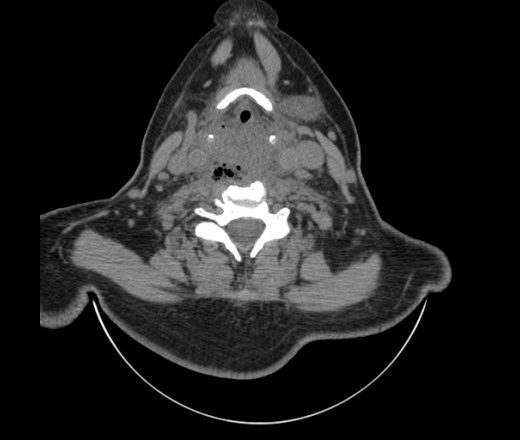

Женщина поступила в х/о спустя 4 дня после того как при употреблении карася подавилась костью.

Наличие газа в средостении на протяжении тел С2-С6 (медиастинальна эмфизема); рыбная кость на уровне тела С6.

При всем уважении, но говорить о медиастинальной эмфиземе, оценивая мягкие ткани шеи, как-то слишком резко. На мой взгляд, это ретрофарингеальное пространство.

Эвакуировали почти 100мл гноя. Но кость не смогли найти. Думаю что она даст дальнейшее ослоднение. Эндоскопически за черпалонадгортаной звязкой не смогли зайти в пищевод, все мягкие ткани отечные, просвет пищевода сдавлен. По всей видимости параэзофагеальная клетчака тоже задействована. Эмпиема, если ее можно так назвать, незнаю как правильно дошла до уровня яремной вырезки. Чем закончиться напишу. Ждем медиастинита.

Флегмона заглоточного пространства шеи, только операция, флегмоны вскрывают. Риск медиастинита.

Согласен с Вами; конечно, наличие газа в клетчатке ретрофарингеального пространства (затмение с опечаткой..). К сожалению, процесс "продвигается" к медиастиниту. Но почему никто, не отмечает наличие рыб. кости; или это для Всех очевидно?

Так вы уже отметили. Хотя ориентировал бы не скелетотопически, а на перстнечерпаловидный сустав.

Кость то мы сразу выявили, размеры где то 17*2мм, но ее так и не получается найти в этой каше